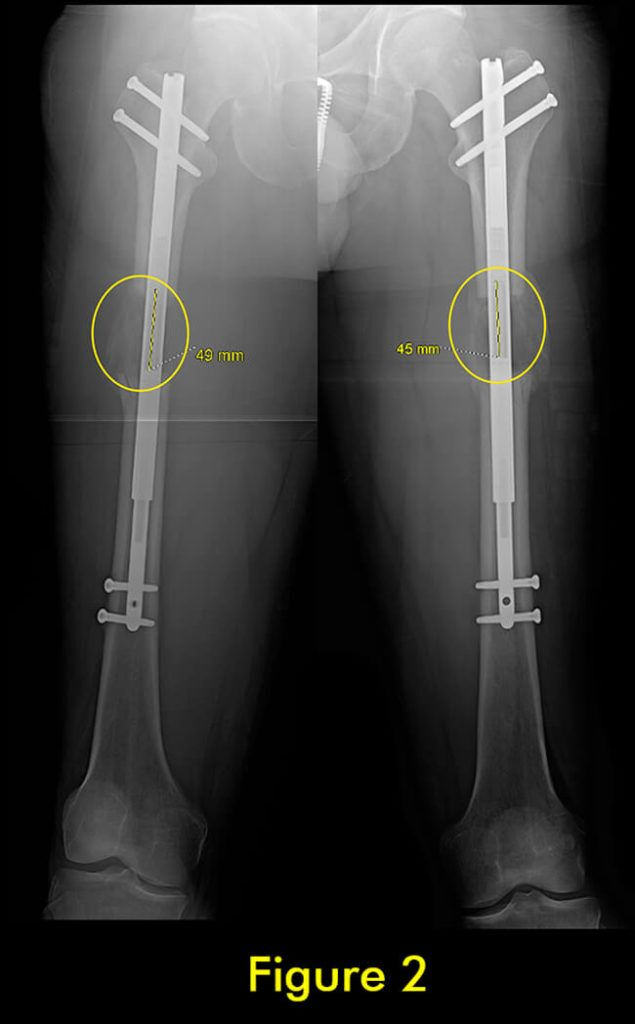

我们为所有患者的腓骨两端固定。植入式加长时,腓骨必须用螺钉固定在胫骨上;上端有一个螺钉,下端有一个螺钉。螺钉的角度、水平、位置、直径和类型都很重要。一个常见的错误是将螺钉水平放入两块骨头之间。这不足以防止腓骨从脚踝处的胫骨上拉开。这是非常微妙的,即使脚踝腓骨长度的几毫米差异也会给患者带来短期和/或长期后果。切除腓骨的一部分以防止腓骨不分离是另一种应避免的常见方法。它会导致腓骨不愈合,从而导致胫骨以后出现应力性骨折。

此外,它通常不会阻止腓骨从胫骨上拉开。因此,腓骨并发症与植入式延长装置的类型无关,而是与外科医生选择将腓骨固定到胫骨的方法和切割腓骨的方法有关。腓骨愈合的范围可以从过早巩固到完全不愈合。后者通常不需要治疗,只要胫骨牢固愈合。前者需要重复腓骨截骨术。

轴向偏斜是胫骨中更常见的问题。胫骨往往会延长成外翻和外翘。为防止这种情况,钉子应插入正确的起点,该起点非常高,并且尽可能靠后,在胫骨的外侧,并在额平面的膝盖中心。如果指甲与截骨术上方的外侧皮层之间有空间,则应在该空间中插入阻挡螺钉。如果指甲与后皮层之间有空间,则在那里插入另一个阻挡螺钉。我设计了 STRYDE 钉子,通过提供第三个近端锁定螺钉(P2.2 只有两个)来抵抗轴向偏差。如果遵循所有这些预防措施,则不会随着延长而出现屈曲或外翻畸形。

在外部机构胫骨身材延长并出现双侧并发症的患者。他发展了胫骨和 Abu/a 延迟结合,右侧是敲击 {外翻),左侧是弓形 {内翻),两侧是 f1exion {procurvatum}。我们在手术室使用临时外部斧头机对两侧进行了急性矫正,并放置了新的胫骨杆。我们在 Abu/a 延迟结合上放置了逆行杆。